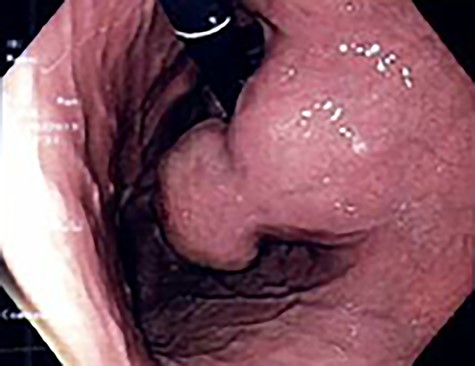

A 56-year-old lady presented with per rectal bleeding and 4 kg weight lost over 1 month. Oesophagogastroduodenoscopy (OGD) performed revealed a large gastric submucosal tumour over the lesser curve (Fig. 1). The proximal margin of the tumour is <1 cm from the GEJ, whereas the distal margin is in the mid lesser curve, about 5 cm proximal to the incisura. Endoscopic ultrasound with fine-needle aspiration performed confirmed the submucosal tumour to be GIST.